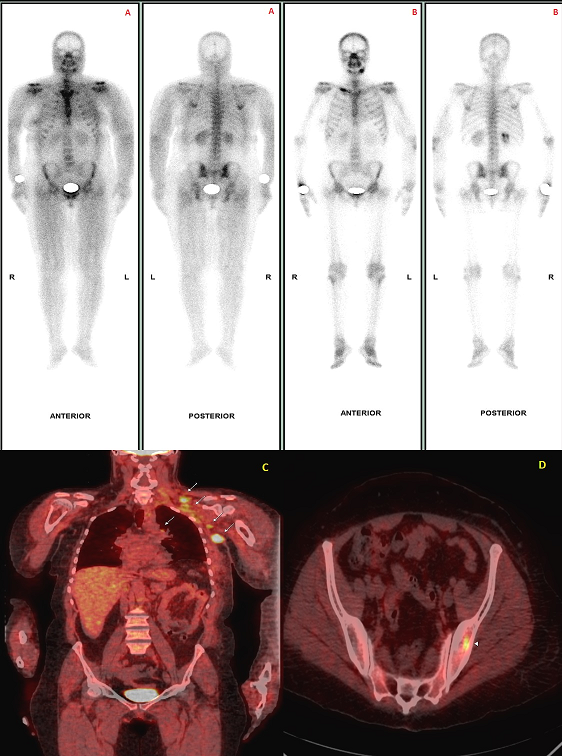

Bone scintigraphy is widely used for initial staging and subsequent follow-up of oncologic patients. 99mTc-labelled diphosphonates also have the ability to detect nonosseous disorders. Muscular uptake on bone scintigraphy has been reported in various conditions including rhabdomyolysis, inflammatory muscle disease, traumatic myositis, polymyositis and dermatomyositis. The proposed mechanism of radiotracer uptake is binding to mitochondrial calcium which is increased in the damaged muscle cells. Here, we report a case of a 62 years old woman with a past history of mastectomy for a galactophoric breast carcinoma, without additional adjuvant treatment, who complained of generalized muscle pain and weakness, erythematous rash on the face, the neck and upper arms. Creatine kinase level was elevated (462 IU/L; normal <200 IU/L). Antinuclear antibodies were negative. These findings with the electromyographic examination (myopathic changes) supported the diagnosis of dermatomyositis. A bone scan performed as a part of the staging process showed diffuse and intense muscular uptake of 99mTc-MDP in the shoulder girdles, both proximal upper and lower limbs corresponding to the sites of symptomatic muscles. No evidence of skeletal involvement was detected (A). PET-CT images showed hypermetabolic foci in multiple thoracic lymph nodes (C) and the left iliac bone (D). A punch biopsy confirmed the diagnosis of metastatic lymph node from a breast carcinoma. Immunosuppressive therapy based on oral prednisone and endoxan followed by molecular targeted therapy (Herceptin and taxotere) improved the myositis and cutaneous eruption. Tree months later, creatine kinase level and muscular uptake of 99mTc-MDP dramatically decreased (B).